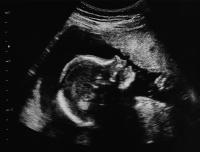

On Monday, the Tennessee House adopted legislation requiring that women wanting information about the abortifacient, RU-486, also be given information about what’s called the Abortion Pill Reversal (APR) technique.

On Wednesday, the U.S. Court of Appeals for the Sixth Circuit, which covers Tennessee, put a final nail in the coffin in Governor Lee’s approach to protecting life beginning with the heartbeat. The governor’s “laddered” abortion bill effectively authorizes the federal courts to decide at which of ten stages of fetal development abortion can be prohibited, beginning with a heartbeat.

On Wednesday, the Tennessee House’s Health Subcommittee, by voice vote, recommended to the full Health Committee both the governor’s proposed abortion legislation, known as the “Missouri laddered” approach, as well as the Rule of Law Life Act.